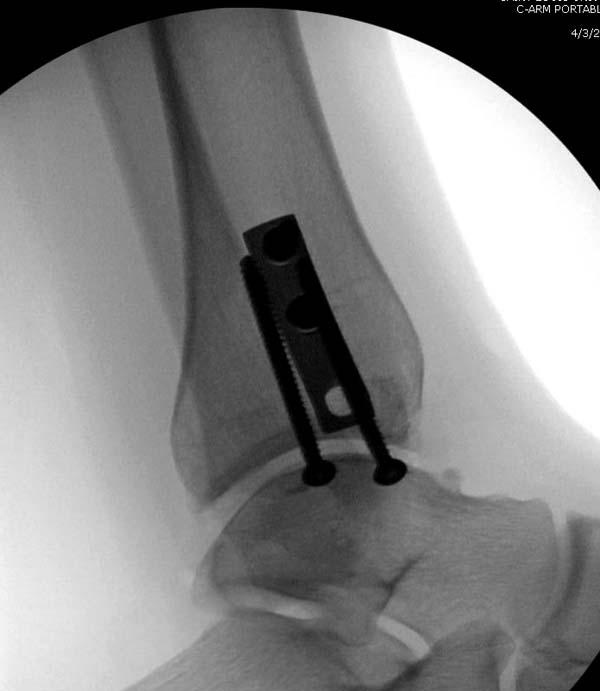

Артроскопия с дебридментом приносит облегчение, но огромные медиально-верхние дефекты надо замещать. Хирургический доступ через медиальную лодыжку, а для замещения применяют современные алломатериалы.

Для ресторации хряща используем хорошо зарекомендовавший продукт компании DeNovo, который полностью восстанавливает повреждение.

И пару дней назад провели операцию... А при огромных дефектах остеохондральный аллографт который выбирается по контуру тарана.